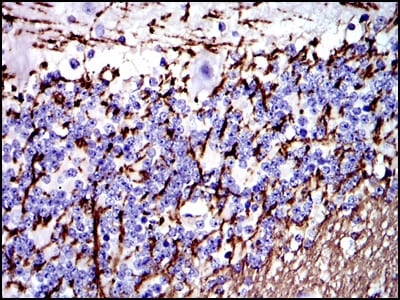

- Immunohistochemical analysis of paraffin-embedded human brain tissues using MBP mouse mAb with DAB staining.

- Immunohistochemical analysis of paraffin-embedded human cerebellum tissues using MBP mouse mAb with DAB staining.